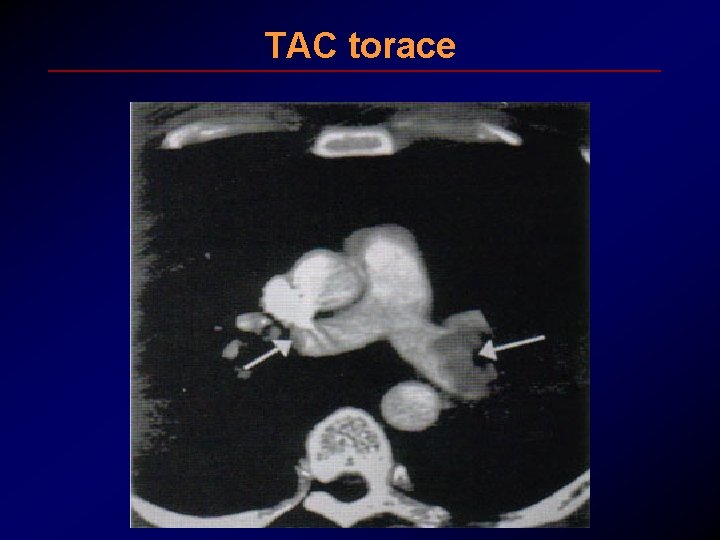

TAC torace